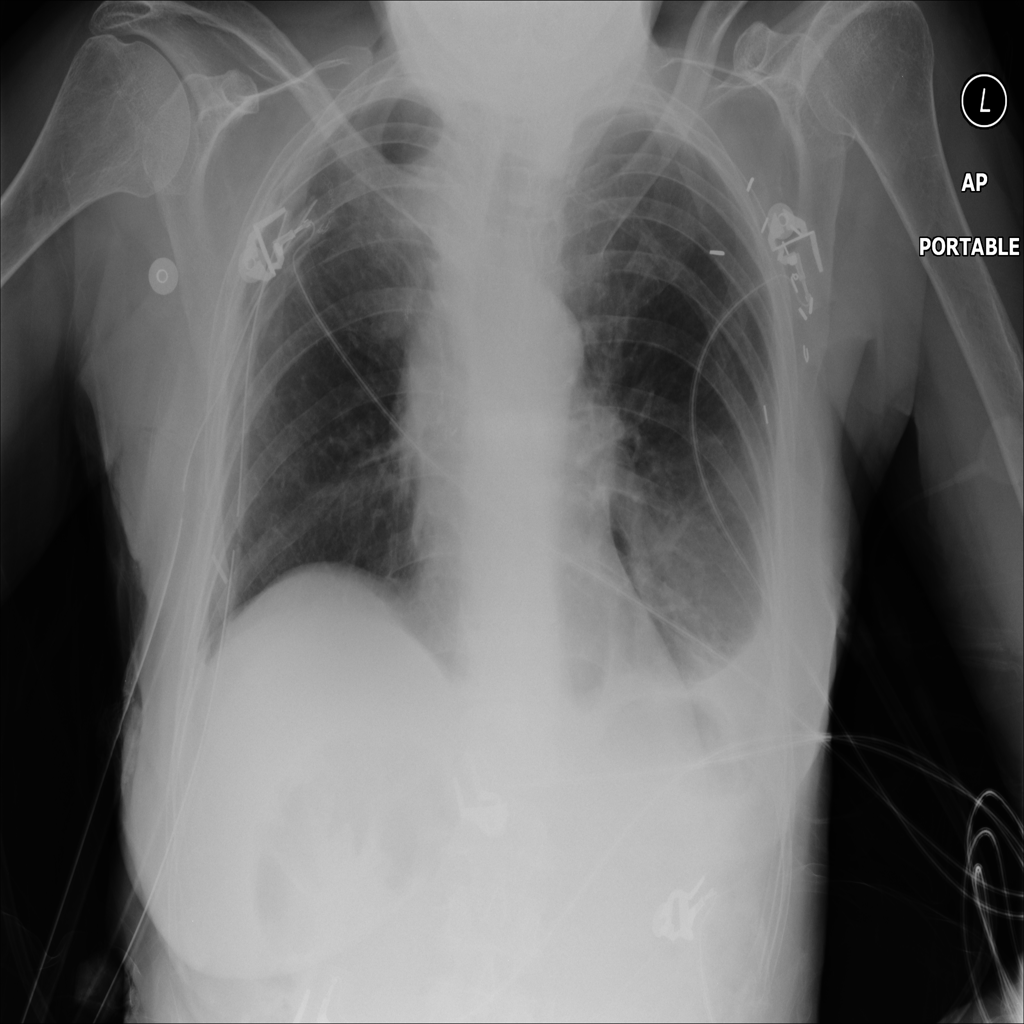

PAT-40F9 · IMG-004Effusion

PAT-40F9 · IMG-004

PA